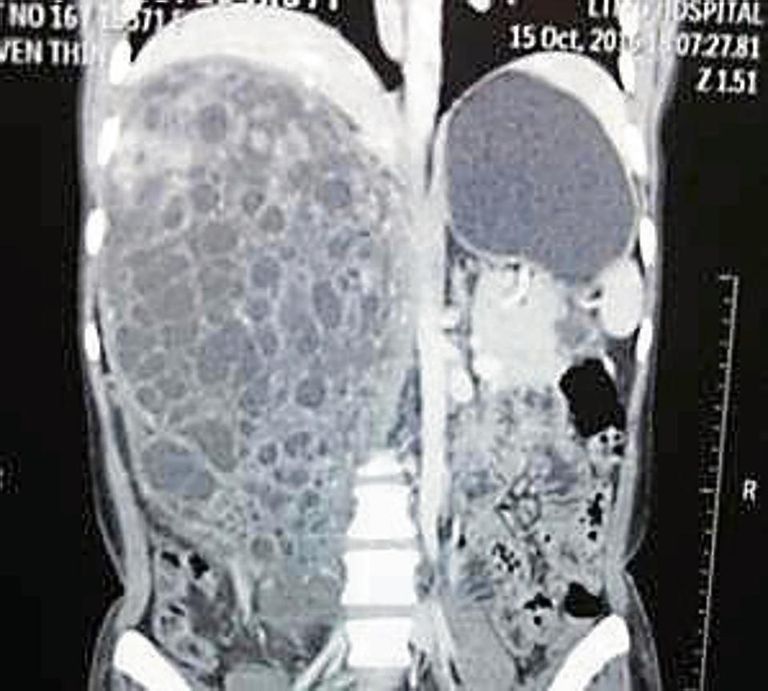

وعندما ذهبت لمستشفى سيون أجرى الأطباء مجموعة من التحاليل والأشعة المقطعية، أظهرت ورما في كلية المريضة، التي كانت تعاني من ألم مستمر في جانبها الأيمن، واختلاط دماء مع البول.

وذكر بيان مستشفى سيون أن تضخم الورم ضغط على الأمعاء والبنكرياس والكبد وأحالهم إلى الجانب الأيسر من البطن، وأُزيل الورم في جراحة طويلة مدتها 8 ساعات، قام بها الدكتور ساوانت والدكتور براكاش بوار وأخصائي التخدير الدكتورة غيتا باتكار والدكتورة أبارنا نيرولكار، في نوفمبر/تشرين الثاني 2016.